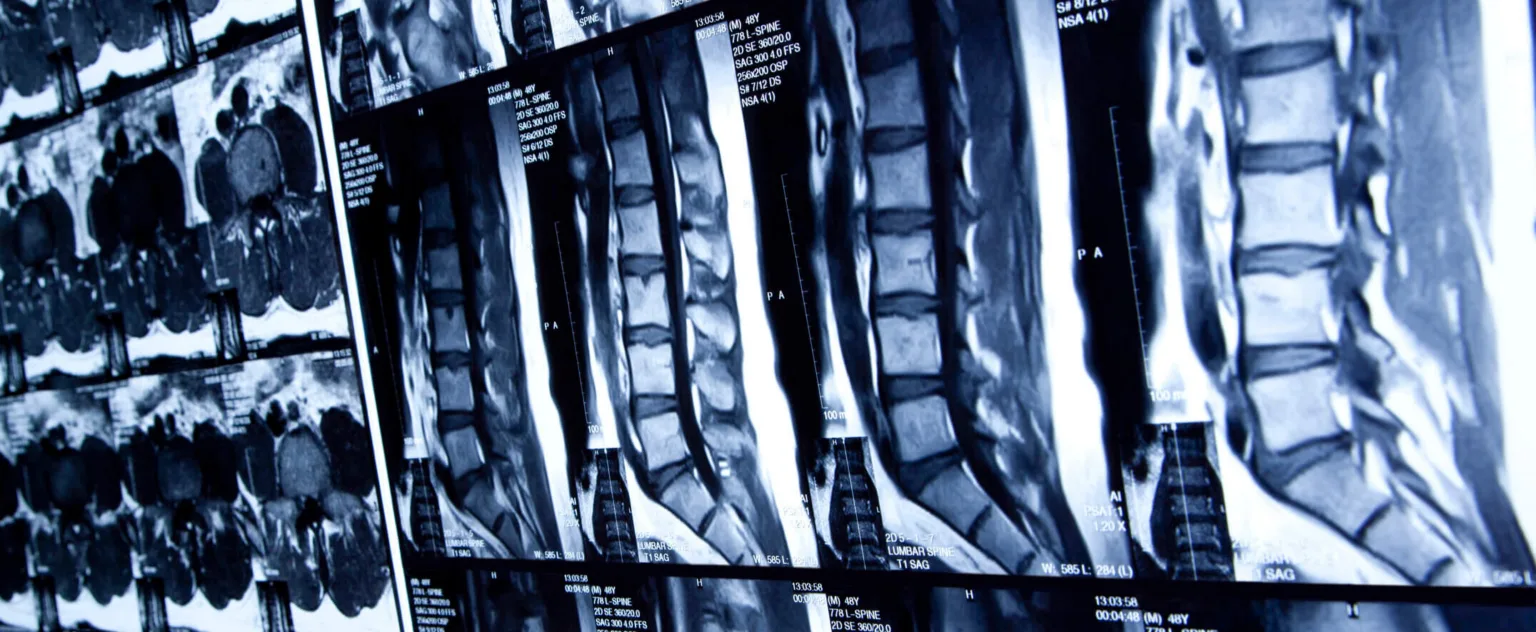

Types of Back Injuries

Back injuries can vary in severity and impact:

- Strains and sprains–Overstretching muscles or ligaments can cause strains and sprains, which can cause pain and limited mobility.

- Herniated discs–When the cushioning discs between vertebrae become damaged or slip out of place, they can compress nerves, leading to intense pain.

- Fractured vertebrae–A broken bone in the spine can cause severe discomfort and potential paralysis if the spinal cord is involved.

- Spinal cord injuries–These injuries can be life-changing, potentially resulting in partial or complete paralysis.